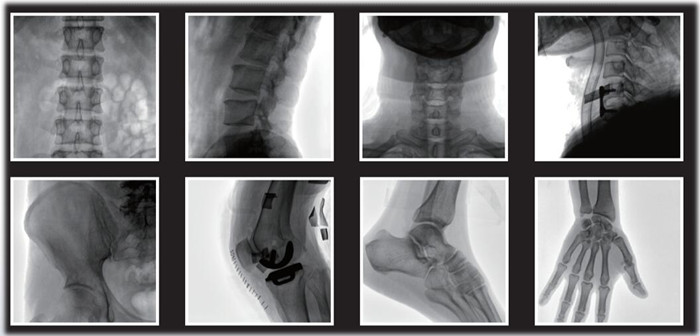

1)小C,骨科手術(shù)必備設(shè)備,也被稱為骨科小C。作為骨科醫(yī)生的眼睛,能在手術(shù)中透視實現(xiàn)準(zhǔn)確定位,輔助醫(yī)生順利、快速、高效完成手術(shù)。目前,小C在我國普及率極高,基本上所有二級及以上醫(yī)院都標(biāo)配小C。

小C在骨科的應(yīng)用是全方位的